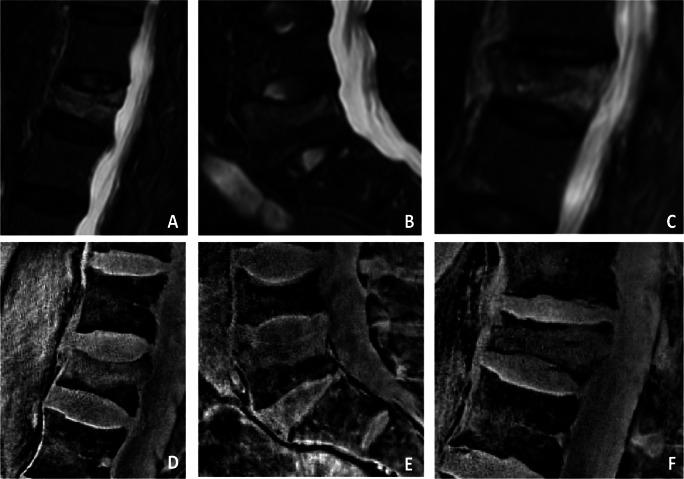

Thirty patients with suspected acute vertebral fractures were examined using a 3-T MRI, including an sUTE sequence as well as short-tau inversion recovery (STIR) and T1-weighted sequences. During postprocessing, water-fat separation was performed by solving the smoothness-constrained inverse water-fat problem based on a single-complex UTE image. By removing the unwanted low-frequency phase terms, additional MR-based susceptibility-weighted-like (SW-like) images with CT-like contrast were created. Two radiologists evaluated semi-quantitative and quantitative features of fractures and degenerative changes independently and separately on CT and MR images.

In total, all 58 fractures were accurately detected of whom 24 were correctly classified as acute fractures with an edema detected on the water-fat-separated UTE images, using STIR and T1w sequences as standard of reference. For the morphological assessment of fractures and degenerative changes, the overall agreement between SW-like images and CT was substantial to excellent (e.g., Genant: κ 0.90 (95% confidence interval 0.54-1.00); AO/Magerl: κ 0.75 (95% confidence interval 0.43-1.00)). Overall inter-reader agreement for water-fat-separated UTE images and SW-like images was substantial to almost perfect.

Detection and assessment of vertebral fractures and degenerative bone changes of the spine were feasible and accurate using water-fat-separated images as well as SW-like images, both derived from the same sUTE-Dixon sequence.

• The detection of acute vertebral fractures was feasible using water-fat-separated images and CT-like images reconstructed from one sUTE sequence. • Assessment of the vertebral fractures using SW-like images with CT-like contrast was found to be comparable to conventional CT. • sUTE imaging of the spine can help reduce examination times and radiation exposure.